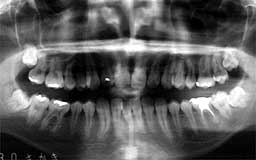

★ Oさん 61歳

Oさんもそんななかのひとりです。来院直後の6年間にブランクがあって、その時失った下

顎の前歯部を除けばかなりの状態をキープしているといえます。61歳としては余りにも条

件が良すぎたためにメインテナンスを積極的に勧めなかったことが少し悔やまれます。

| Oさん 初診時 61歳 男性 上顎臼歯部に中程度以上の歯槽骨破壊が認められるが残存する歯の数は多い |

Oさん 20年後 81歳歳 補綴(ほてつ)物が多いことに不満を感じるが親知らずを含む残存歯数27本は立派 |